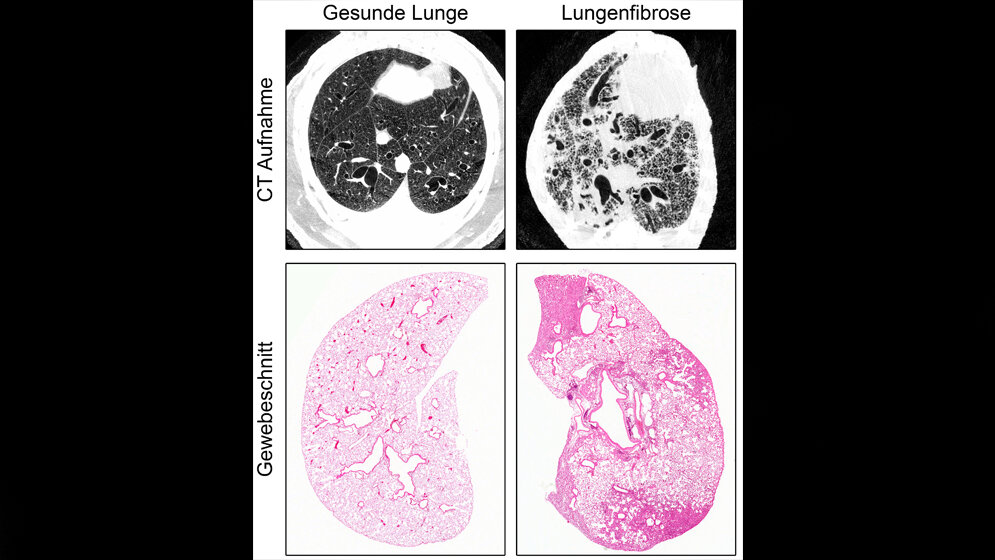

NEDD4-2 ist für die frühe Entwicklung unverzichtbar und das kodierte Gen wurde erst bei erwachsenen Tieren in der Lunge entfernt. Zu einem späteren Zeitpunkt, der dem der Diagnosestellung beim Patienten gleichkommt, wurde es wieder untersucht. Messungen der Sauerstoffsättigung bestätigten dabei eine für die Erkrankung typische Verschlechterung der Lungenfunktion. Auch strukturelle Kennzeichen einer Fibrose wie eine fleckige Vernarbung waren durch eine Computertomografie zu erkennen.

Eine Untersuchung der Gesamtheit aller Proteine ergab eine hohe Übereinstimmung an Proteinen, die sowohl beim Patienten mit IPF als auch im Tiermodell veränderte Expressionen aufweisen. NEDD4-2 ist für die Entstehung einer Fibrose bedeutsam, da sowohl die Transkript- als auch die Proteinmenge in Lungenbiopsien stark reduziert sind. Die Erkenntnisse der Forscher sollen nun weitere Untersuchungen zu Entstehung und Verlauf der Fibrose ermöglichen, ebenso wie die Entwicklung neuer Therapien oder eine Früherkennung der Krankheit.